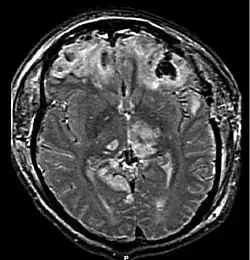

MRI showing damage due to herniation. This patient was left with residual disabilities including those involving movement and speech.[16]

Treatment involves removal of the etiologic mass and decompressive craniectomy. Brain herniation can cause severe disability or death. In fact, when herniation is visible on a CT scan, the prognosis for a meaningful recovery of neurological function is poor.[2] The patient may become paralyzed on the same side as the lesion causing the pressure, or damage to parts of the brain caused by herniation may cause paralysis on the side opposite the lesion.[11] Damage to the midbrain, which contains the reticular activating network which regulates consciousness, will result in coma.[11] Damage to the cardio-respiratory centers in the medulla oblongata will cause respiratory arrest and (secondarily) cardiac arrest.[11] Investigation is underway regarding the use of neuroprotective agents during the prolonged post-traumatic period of brain hypersensitivity associated with the syndrome.[17]